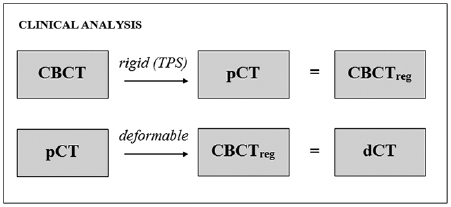

Demonstration of clinical application

Following validation of the accuracy of the registrations, the intended clinical procedure was demonstrated retrospectively for a single patient within the sample (Patient 5). Four CBCTs that were obtained prior to the patient replan (including the one used in the validation exercises above) were used to generate dCTs. For this particular analysis, the CBCT was first rigidly registered to the pCT using online registration parameters obtained from the TPS (figure 4). This ensured that the dose distribution derived from the dCT also incorporated residual setup errors, as it would in a real clinical scenario. Dose distributions and DVHs were calculated using deformed pCT structures. A visual appraisal of the deformed structures was carried out with reference to both the dCT and CBCT to check for any obvious mismatches in anatomy.

Figure 4. Pipeline of the registrations carried out to produce deformed pCT images for clinical analysis.

Download figure:

Standard image High-resolution imageChanges to the dose distribution over the course of treatment were then evaluated, taking into consideration the clinical objectives for this patient's treatment plan.